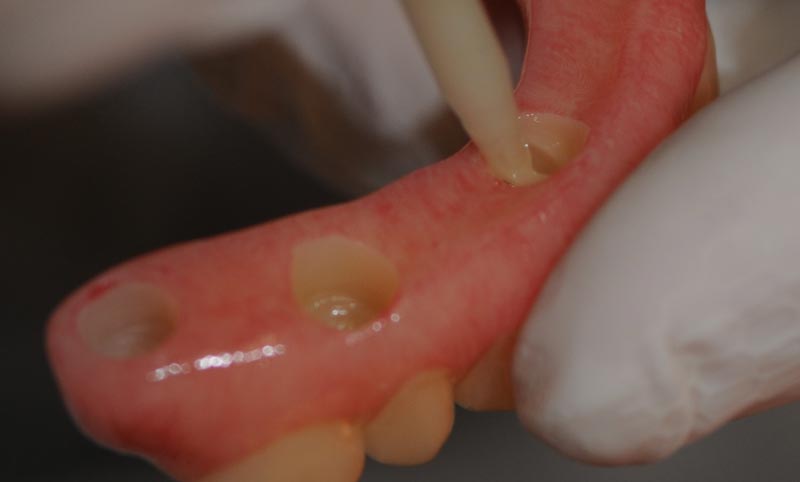

Cappette Fixed sui monconi conometrici

Fissaggio della protesi con cemento